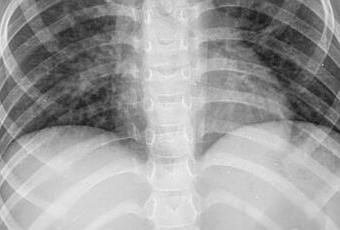

Se observa radiografía posteroanterior de tórax encontrando los siguientes hallazgos:

El parénquima pulmonar se observa discreto aumento de la radiodensidad pulmonar de aspecto nodular inespecífico como datos incipientes de bronconeumonía.

DISCRETO AUMENTO DE LA RADIODENSIDAD PULMONAR DERECHA COMO DATOS INCIPIENTES DE BRONCONEUMONIA CORRELACIONAR CON DATOS CLINICOS.